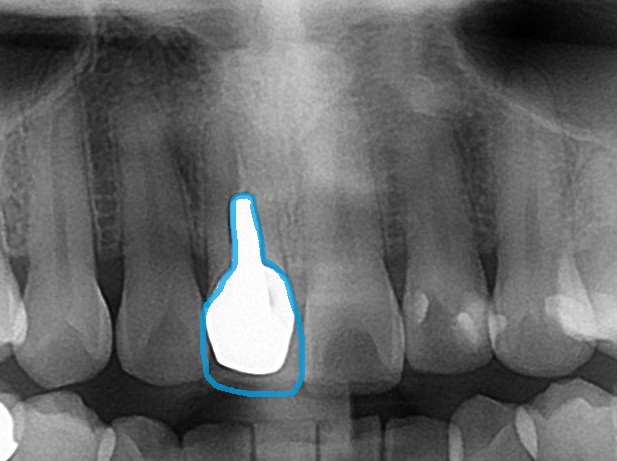

青い部分が白く写っており、メタルコアという金属の土台が埋め込まれています。

当院で根管治療をした後のレントゲン写真を載せておきますが

根管治療を行ない、消毒した根管を薬剤で密閉しています。材料がレントゲン写真で白く写るので、根管治療がしてあるのが分かります。